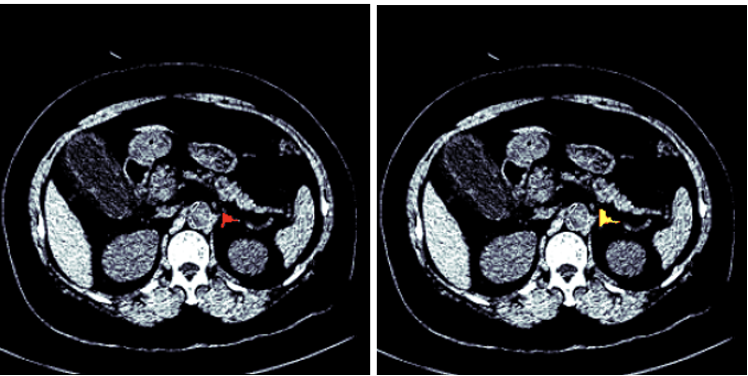

Figures 1 and 2 show the segmented model output for both right and left adrenal gland from a CT scan image from the AMOS dataset.

Figure 1: Segmentation of a right adrenal gland (AMOS dataset)